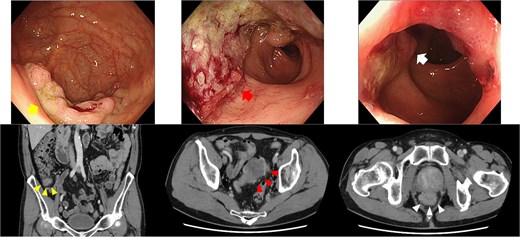

A 73-year-old man with a body mass index of 22.6 kg/m2 and no significant past medical history presented with bowel movement irregularities and unintentional weight loss. Colonoscopy revealed three distinct lesions: a laterally spreading tumor in the cecum, a semi-circumferential type 2 lesion in the sigmoid colon, and another semi-circumferential type 2 lesion in the lower rectum (Rb). Biopsies confirmed a cecal adenoma, a mucinous adenocarcinoma in the sigmoid colon, and a moderately differentiated adenocarcinoma in the rectum.

Contrast-enhanced computed tomography (CT) demonstrated bowel wall thickening in all three sites, with regional lymphadenopathy observed in the sigmoid and rectal mesenteries. No distant metastasis was identified (Fig. 1). Given the proximity of the rectal tumor to the anal verge (within 1 cm), sphincter preservation was deemed infeasible, and abdominoperineal resection was planned. Although endoscopic resection was initially considered for the cecal lesion, surgical resection was chosen following multidisciplinary consultation.

Endoscopy and enhanced CT endoscopy showed tumors in the cecum (LST-G, upper left), sigmoid (type 2, upper middle), and rectum (type 2, upper right). Enhanced CT provided important insights into the wall thickness in the cecum (lower left), sigmoid colon (lower middle), and rectum (lower right).